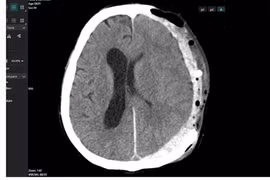

(khoahocdoisong.vn) - Chấn thương sọ não nặng được điều trị bằng phẫu thuật, hồi sức hoặc phối hợp. Kết quả hồi sức và điều trị bệnh nhân chấn thương sọ não nặng phụ thuộc vào nhiều yếu tố như tuổi, tình trạng bệnh nhân, tổn thương tại não, tổn thương phối hợp, thời điểm điều trị.

(khoahocdoisong.vn) - Chấn thương sọ não thường bắt nguồn từ các loại chấn thương về não bao gồm chảy máu, chấn động mạnh, rung động não hoặc não bị bầm.